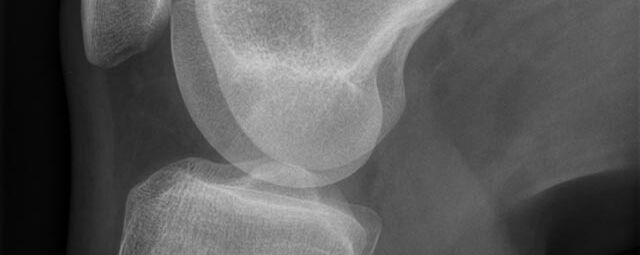

Röntgen Knochen

Röntgenaufnahme einer Hand

• Fraktur

• Arthrose

• Rheumatische Gelenkerkrankungen

• Degenerative Veränderungen der Wirbelsäule

• Knochentumor

• Osteoporose

• Therapiekontrolle nach OP am Skelettsystem

• Vollautomatische Erstellung von Ganzbein- und Ganzwirbelsäulenaufnahmen